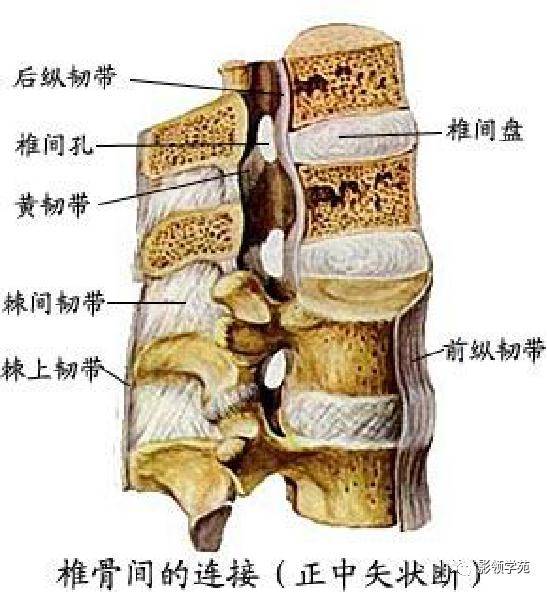

关节与韧带系统

韧带系统

关节与韧带系统

韧带系统